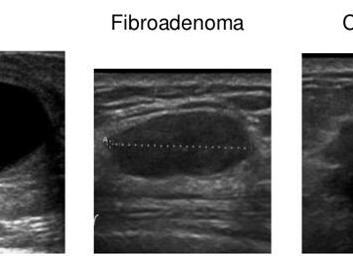

На фото представлена УЗИ-картина фиброаденомы (слева) и рака (справа) молочной железы.

Фиброаденома выглядит как четко-ограниченное гипоэхогенное образование с ровными или дольчатыми контурами в отличие от рака. Злокачественная опухоль характеризуется неровными краями и атипическим ростом.